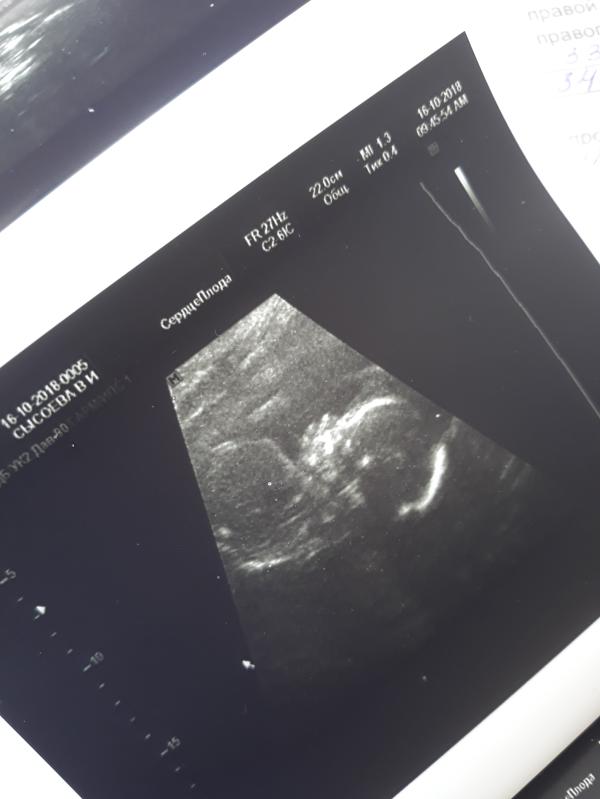

Второй скрининг позади))) подтвердили девочку 100%. На узи мы сосали палец, зевали, закрывали лицо рукой. Губы сказали пухлые, как у мамы))))